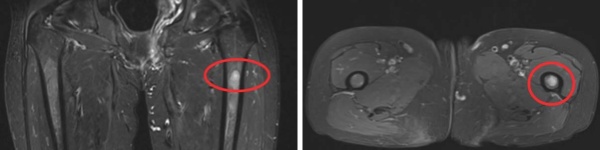

MRI 影像:左股骨髓腔内可见明确异常信号,病灶范围清晰可见;

CT 扫描:骨质破坏特征显著;

骨扫描:左股骨代谢活跃,提示肿瘤活性。

经多学科会诊(MDT),团队制定“微波消融+骨水泥填充”微创个性化方案。术中在C型臂精准引导下,直径仅2毫米的消融针直达肿瘤核心,通过高频微波产生100℃以上高温,实现肿瘤组织瞬间凝固性坏死,同时注入骨水泥强化骨骼支撑。术后复查X线显示消融范围覆盖病灶,骨水泥填充稳定。